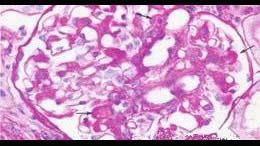

问题 阅读下述两张病理图片(光镜PAS染色,免疫荧光IgA阳性)后,可诊断 ( )

选项 A.新月体性肾小球肾炎 B.系膜增生性肾小球肾炎 C.膜增生性肾小球肾炎 D.局灶性节段性硬化 E.IgA肾病

答案 E